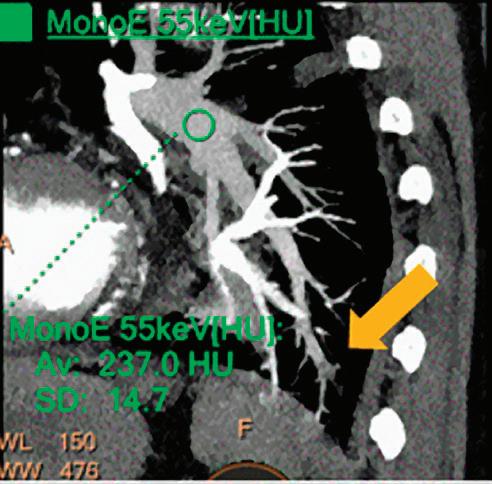

CT breath-hold results in a poor enhancement of the pulmonary arteries on the displays from left to right: monoenergetic 70 keV, monoenergetic 55 keV, monoenergetic 40 keV, and Z effective map showing a perfusion deficit of the lung parenchyma (white arrow). When decreasing the energy, the iodine attenuation is progressively boosted and reveals the presence of a thrombus (colored arrows) in a sub-segmental pulmonary artery corresponding to the territory of the perfusion deficit. (c) Monoenergetic 200 keV reduces beam hardening from dense contrast medium compared to conventional CT images.

Once the pair (αp, αc) is calculated for every voxel, and since fp(E) and fc(E) are known functions of energy, one may synthesize monochromatic images at different energies. These images can be used for routine diagnosis similar to conventional images. With a single scan at 120 kVp (or 140 kVp for obese patients), a dual-layer spectral CT acquisition allows the reconstruction of virtual monochromatic images from 40 keV up to 200 keV, in increments of 1 keV. The minimum of 40 keV was chosen in order to stay above the k-edge of the most common materials including iodine (iodine k-edge = 33 keV). If the scan is performed at 120 kVp, the conventional CT images of a typical-size patient will display an attenuation corresponding to the average of the X-ray spectrum (˜70 keV in a body scan) but with beam hardening artifacts from dense structures (like bones) which are due to the polychromatic nature of the X-ray beam. Since the photoelectric effect is dominant at lower keV, and is relatively high for high Z materials, low keV imaging (below 70 keV for body) can be used to enhance the absorption of high Z material such as iodine (Z=53), compared to the conventional CT images.15,16 This can be of particular interest to enhance the iodine uptake for patients with renal dysfunction, where the total injected volume of iodinated contrast medium is very limited. This attenuation boost can also be very useful in the case of a missed injection (Figure 2a and b). Compton scattering on the other hand is dominant at higher keVs and does not exhibit a strong relationship with Z. High keV imaging will then be of particular interest to minimize the absorption of high Z materials and minimize all types of associated artifacts (metal beam hardening from metal implants, beam hardening from dense contrast medium, blooming of stents or calcium, etc.) (Figure 2c).17,18,19

Virtual monoenergetic images obtained from the IQon Spectral CT scanner have low noise across the entire spectrum of energies,20 and this noise is lower than in conventional images due to the spectral reconstruction processing that includes noise suppression algorithms that make use of the additional spectral information. This provides significant SNR and CNR improvements compared to conventional polyenergetic images. The low noise of monoenergetic images at various energy levels makes them usable at all energy levels, particularly at low energies for enhancing vascular contrast or improving lesion conspicuity and at higher energies for decreasing artifacts.